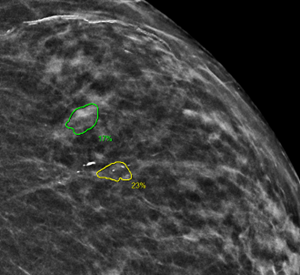

PowerServer now supports Computer-Aided Detection (CAD) 3D Navigation, enabling enhanced volumetric image analysis and interactive visualization tools to support more accurate diagnostic interpretation. Feature is activated when a study has CAD objects. In Volume (DBT) MG, the slice option would show up, allowing the user to navigate to the slice with the CAD finding by clicking on the slice number (Figure 4).

Figure 4 Slice navigation is done by clicking on the slice number

In addition to navigation, 6.7 also supports color coding of CAD findings (Figure 5). This feature is only available in iCAD generated objects.

Figure 5 Based on the iCAD score CAD findings are color coded